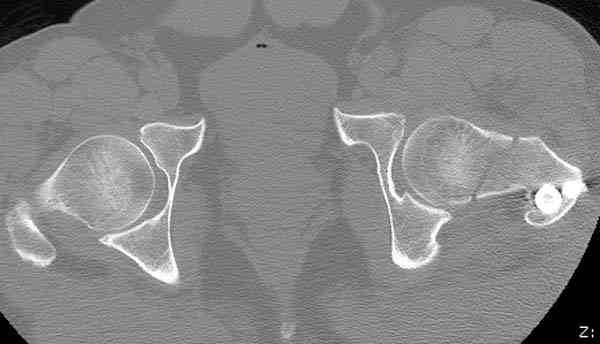

Здесь представлены снимки больного 65 лет, поступившего с диагнозом перелом

бедра после автоаварии.

В первый же день произведено антеградное штифтованием DePuy Trochanteric Nail.

На второй день (7) обнаружен пропущенный перелом,

сделаны Компьютерная Томограмма

и проведены шурурпы через и спереди штифта без удаления.

Послеоперационные снимки